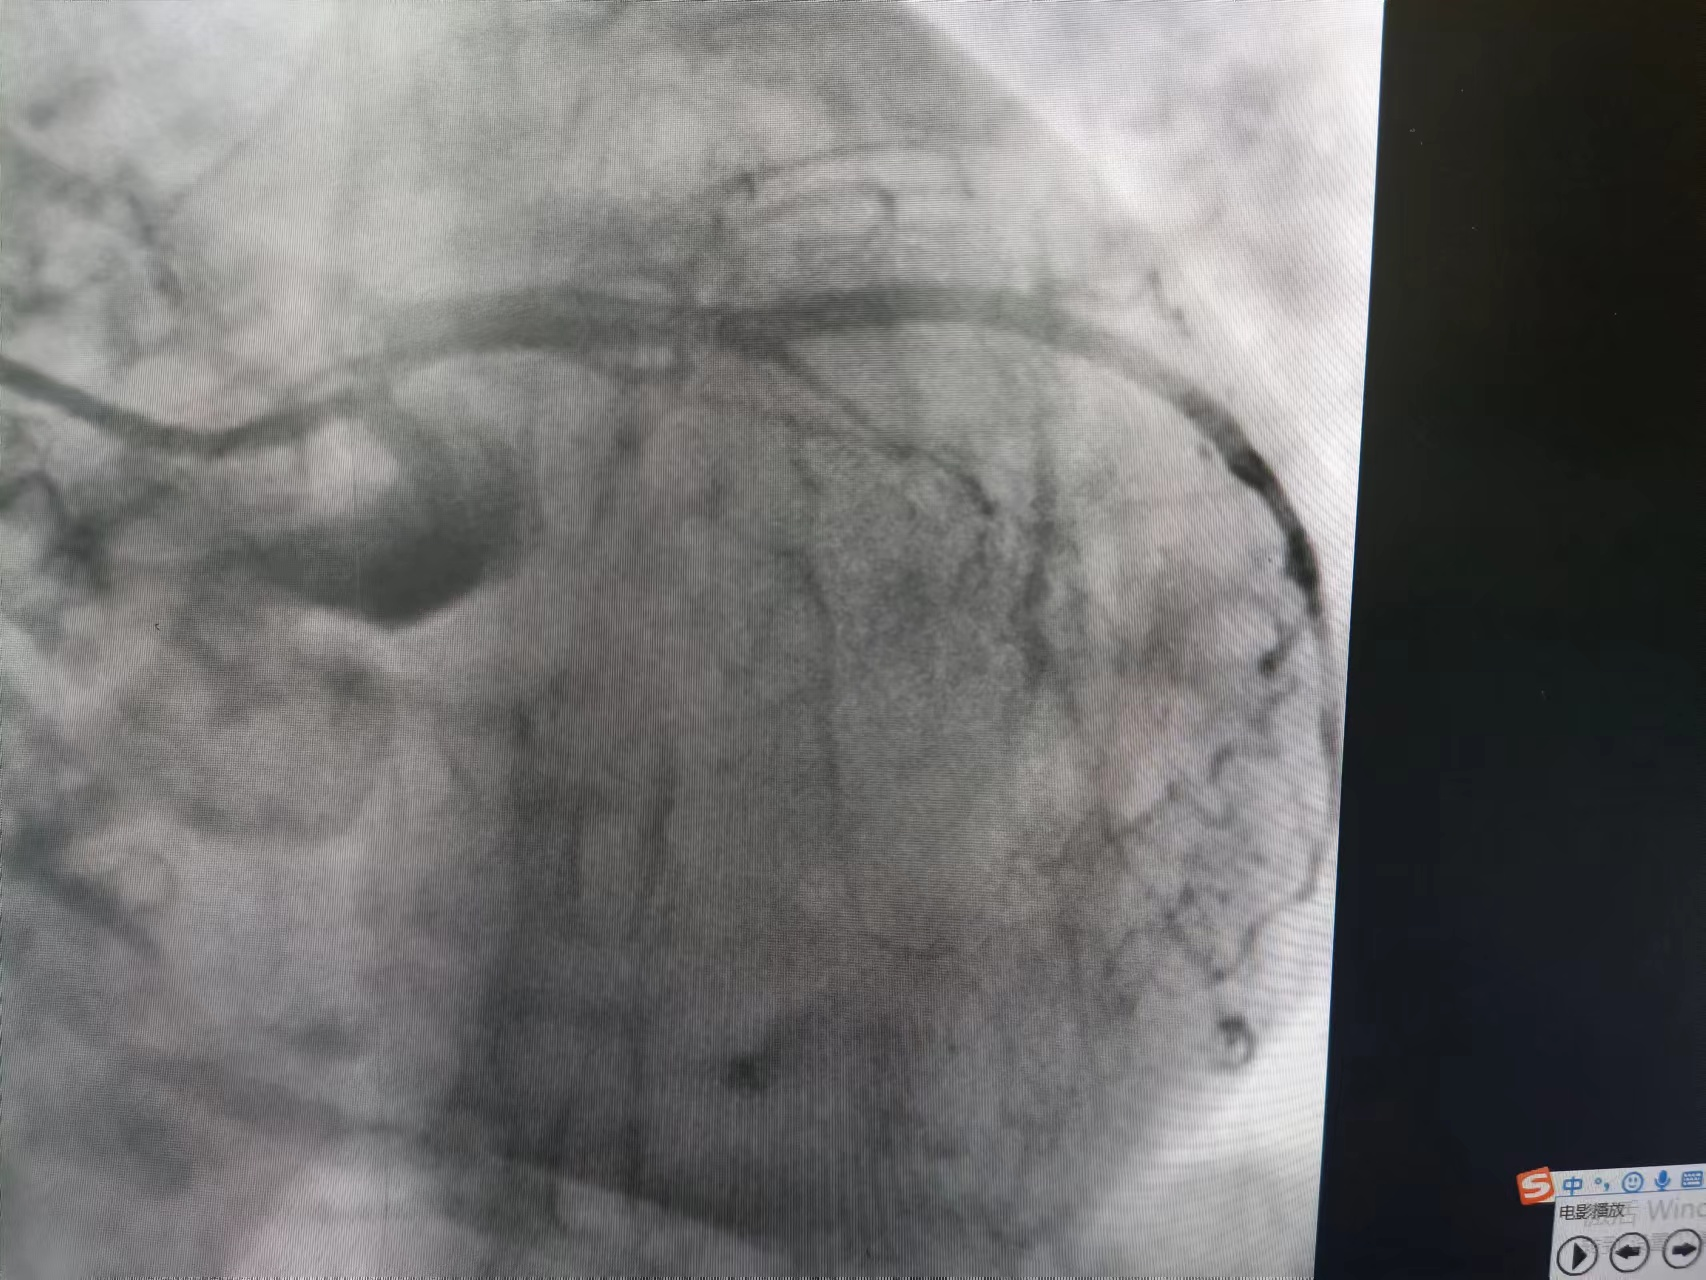

患者系102岁的超高龄女性,突发胸闷,伴大汗、乏力。外院就诊行心电图检查提示“心房颤动,II、III、AVF导联ST段显著抬高”,诊断急性下壁心肌梗死。由于患者体质差,年龄大等因素,当地医院转入我院,该患者合并房颤、血压低、精神差、症状重,生命危在旦夕,为救治患者,我院胸痛中心迅速启动导管室绿色通道,急诊行冠脉介入治疗。![]() 患者入介入室时已存在早期休克表现,脉搏微弱,桡动脉穿刺难度大,急诊备班的易主任凭借丰富的经验和高超的桡动脉穿刺技术,迅速为患者成功植入了桡动脉鞘管,并小心通过上肢扭曲的动脉顺利完成造影。经造影提示患者前降支开口闭塞,右冠脉开口闭塞,回旋支中段后闭塞,目前该患者仅有单支血管供血,心脏搏动微弱,随时可能发生死亡。易勇副主任争分夺秒,极短时间内顺利开通此次罪犯血管右冠脉,但植入支架后出现明显慢血流的情况,经给予硝普钠及反复冠脉抽吸处理后,患者血流恢复,成功完成手术。

![]() ![]() ![]() 术前冠脉造影